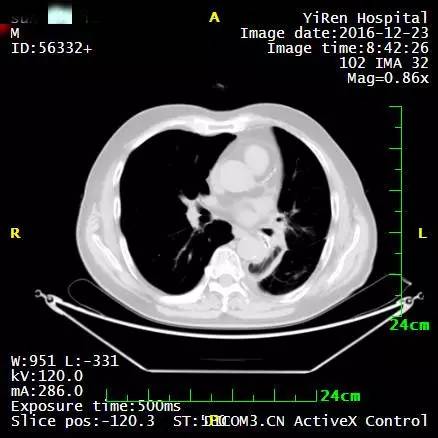

2、患者男性,64岁,小细胞肺癌

2016年3月,王先生因咳嗽加重就诊于当地医院,支气管镜病理检查提示:考虑小细胞癌的可能性大。

化疗一周期,病情无改善症状加重。

2016年4月,王先生接受了A45治疗,一个月后复查,病灶明显缩小,2016年7月复查,病灶进一步缩小,因为A45治疗具有明显的远观效应,能够激发自身的免疫系统,长期有效的消灭体内肿瘤,2016年12月,王先生肺部病灶几乎全部消失。

治疗前

治疗后

治疗后两个月

治疗后7个月

目前王先生状态良好,没有任何复发迹象。